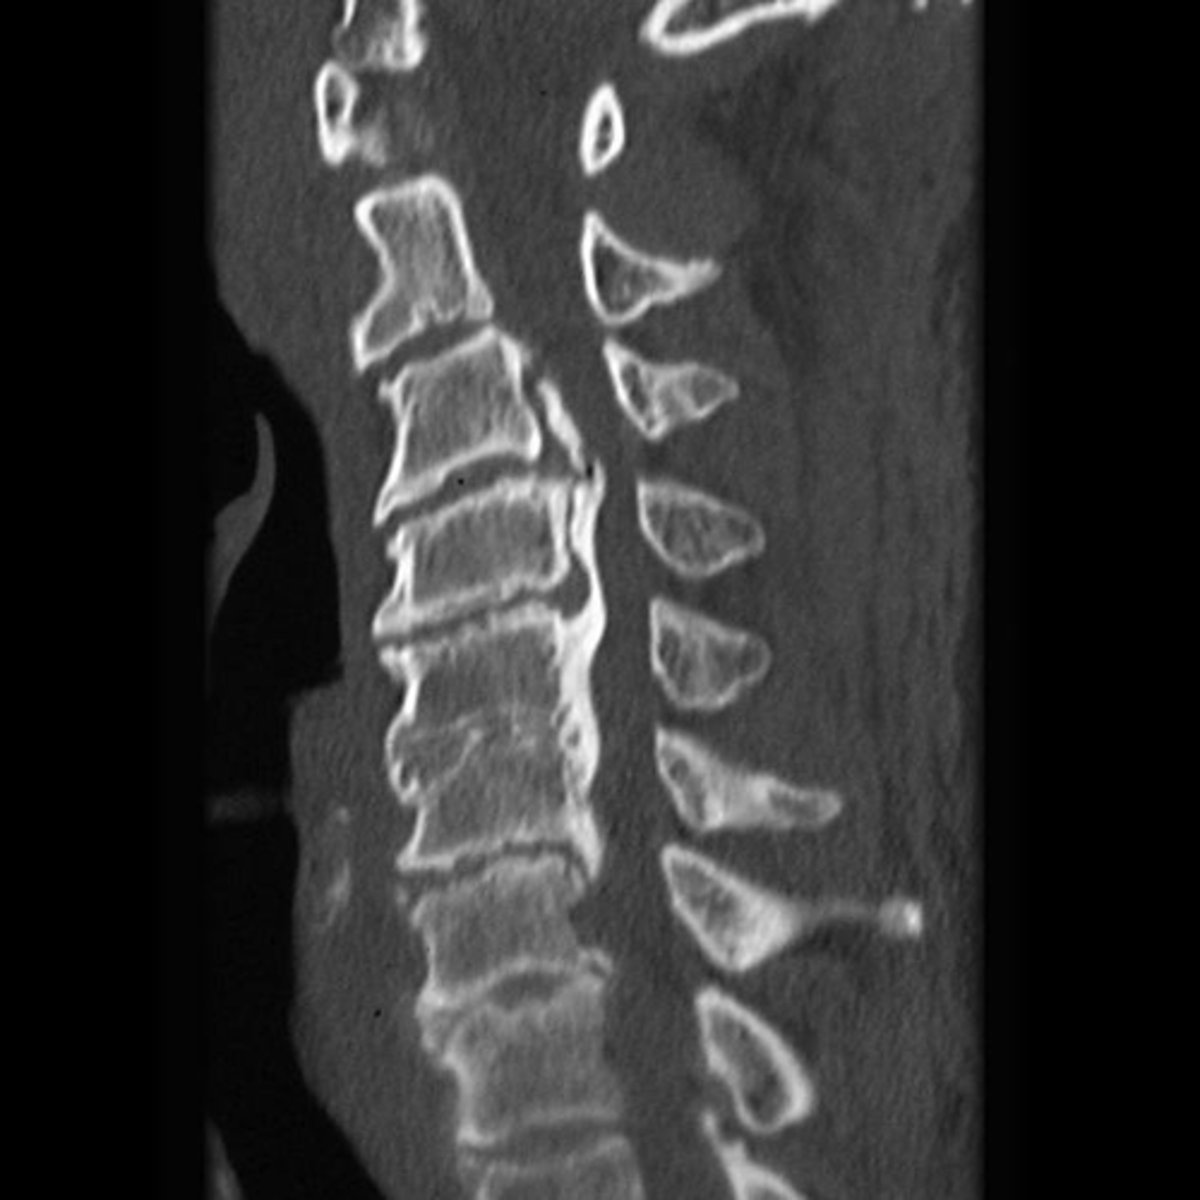

Ossification of the posterior longitudinal ligament (OPLL)

What is the main finding on the CT study?

Diffuse idiopathic skeletal hyperostosis (DISH)

Most likely diagnosis?

Neurosurgeon referral

Next step?

No

Would you adjust this patient's cervical spine?